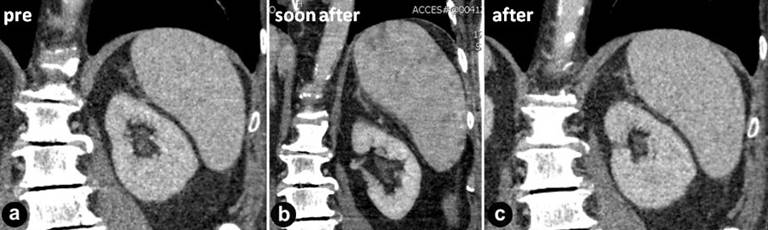

The patient was discharged after 4 days and he reported a complete regression of pain, with a score of 0/10 [10]. One month after IRE procedure, a CT scan was performed and it demonstrated an absence of enhancement within the expected ablation zone. Splenic artery remained patent and the spleen was homogenous, in particular no vascular defects or infarcts were revealed in its parenchyma (Figure 5abc).

Figure 5. Coronal CT images compared splenic parenchyma before (a.), soon after (b.) and 1 month after (c.) the procedure. |